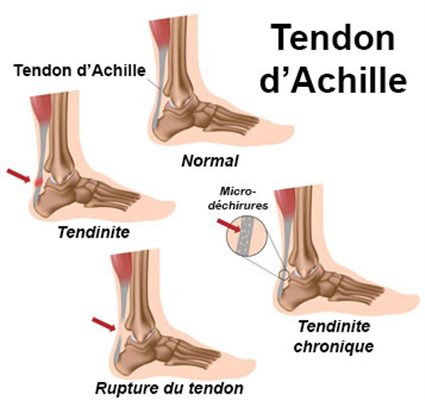

Tendinopathie achilléenne

La tendinite du tendon d’Achille est une inflammation de

ce tendon situé en dessous du mollet qui survient à la suite d’efforts répétitifs, trop

prononcés ou encore à la prise de certains médicaments comme les quinolones qui

fragilisent le tendon et peuvent même aboutir à la rupture.

Une paire d’orthèse plantaire est réalisée en traitement complémentaire aux séances de kinésithérapie prescrites par le médecin. Elles seront portées pendant toute la durée des séances et régulièrement réduites par ponçage pour accompagner la rééducation.